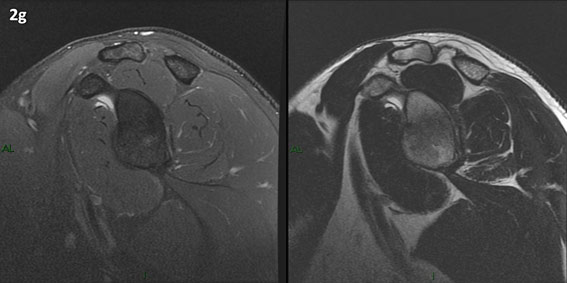

Figura 2 (a-j): Imagens consecutivas de RM no plano sagital nas ponderações T2 com supressão de gordura (DP SG) à esquerda e T2 à direita. Clique na seta para passar as imagens.

Figura 2 (a-j)': Imagens consecutivas de RM no plano sagital nas ponderaçõesT2 com supressão de gordura (DP SG) à esquerda e T2 à direita. Clique na seta para passar as imagens.

Figura 2a’ mostrando os tendões do subescapular (seta rosa), da cabeça longa do bíceps (seta verde), do supraespinhal (seta vermelha), do infraespinhal (seta laranja) e do redondo menor (seta amarela).

Figuras 2b a 2j’: Acompanhando o tendão do redondo menor (seta amarela fina) é possível notar lipossubstituição ao redor da junção miotendínea (setas amarelas grossas) e a atrofia principalmente da porção mais lateral (seta salmão). A porção mais medial (seta branca) tem volume preservado.

Repare que estas alterações também não são evidentes nas imagens com supressão de gordura no plano sagital.